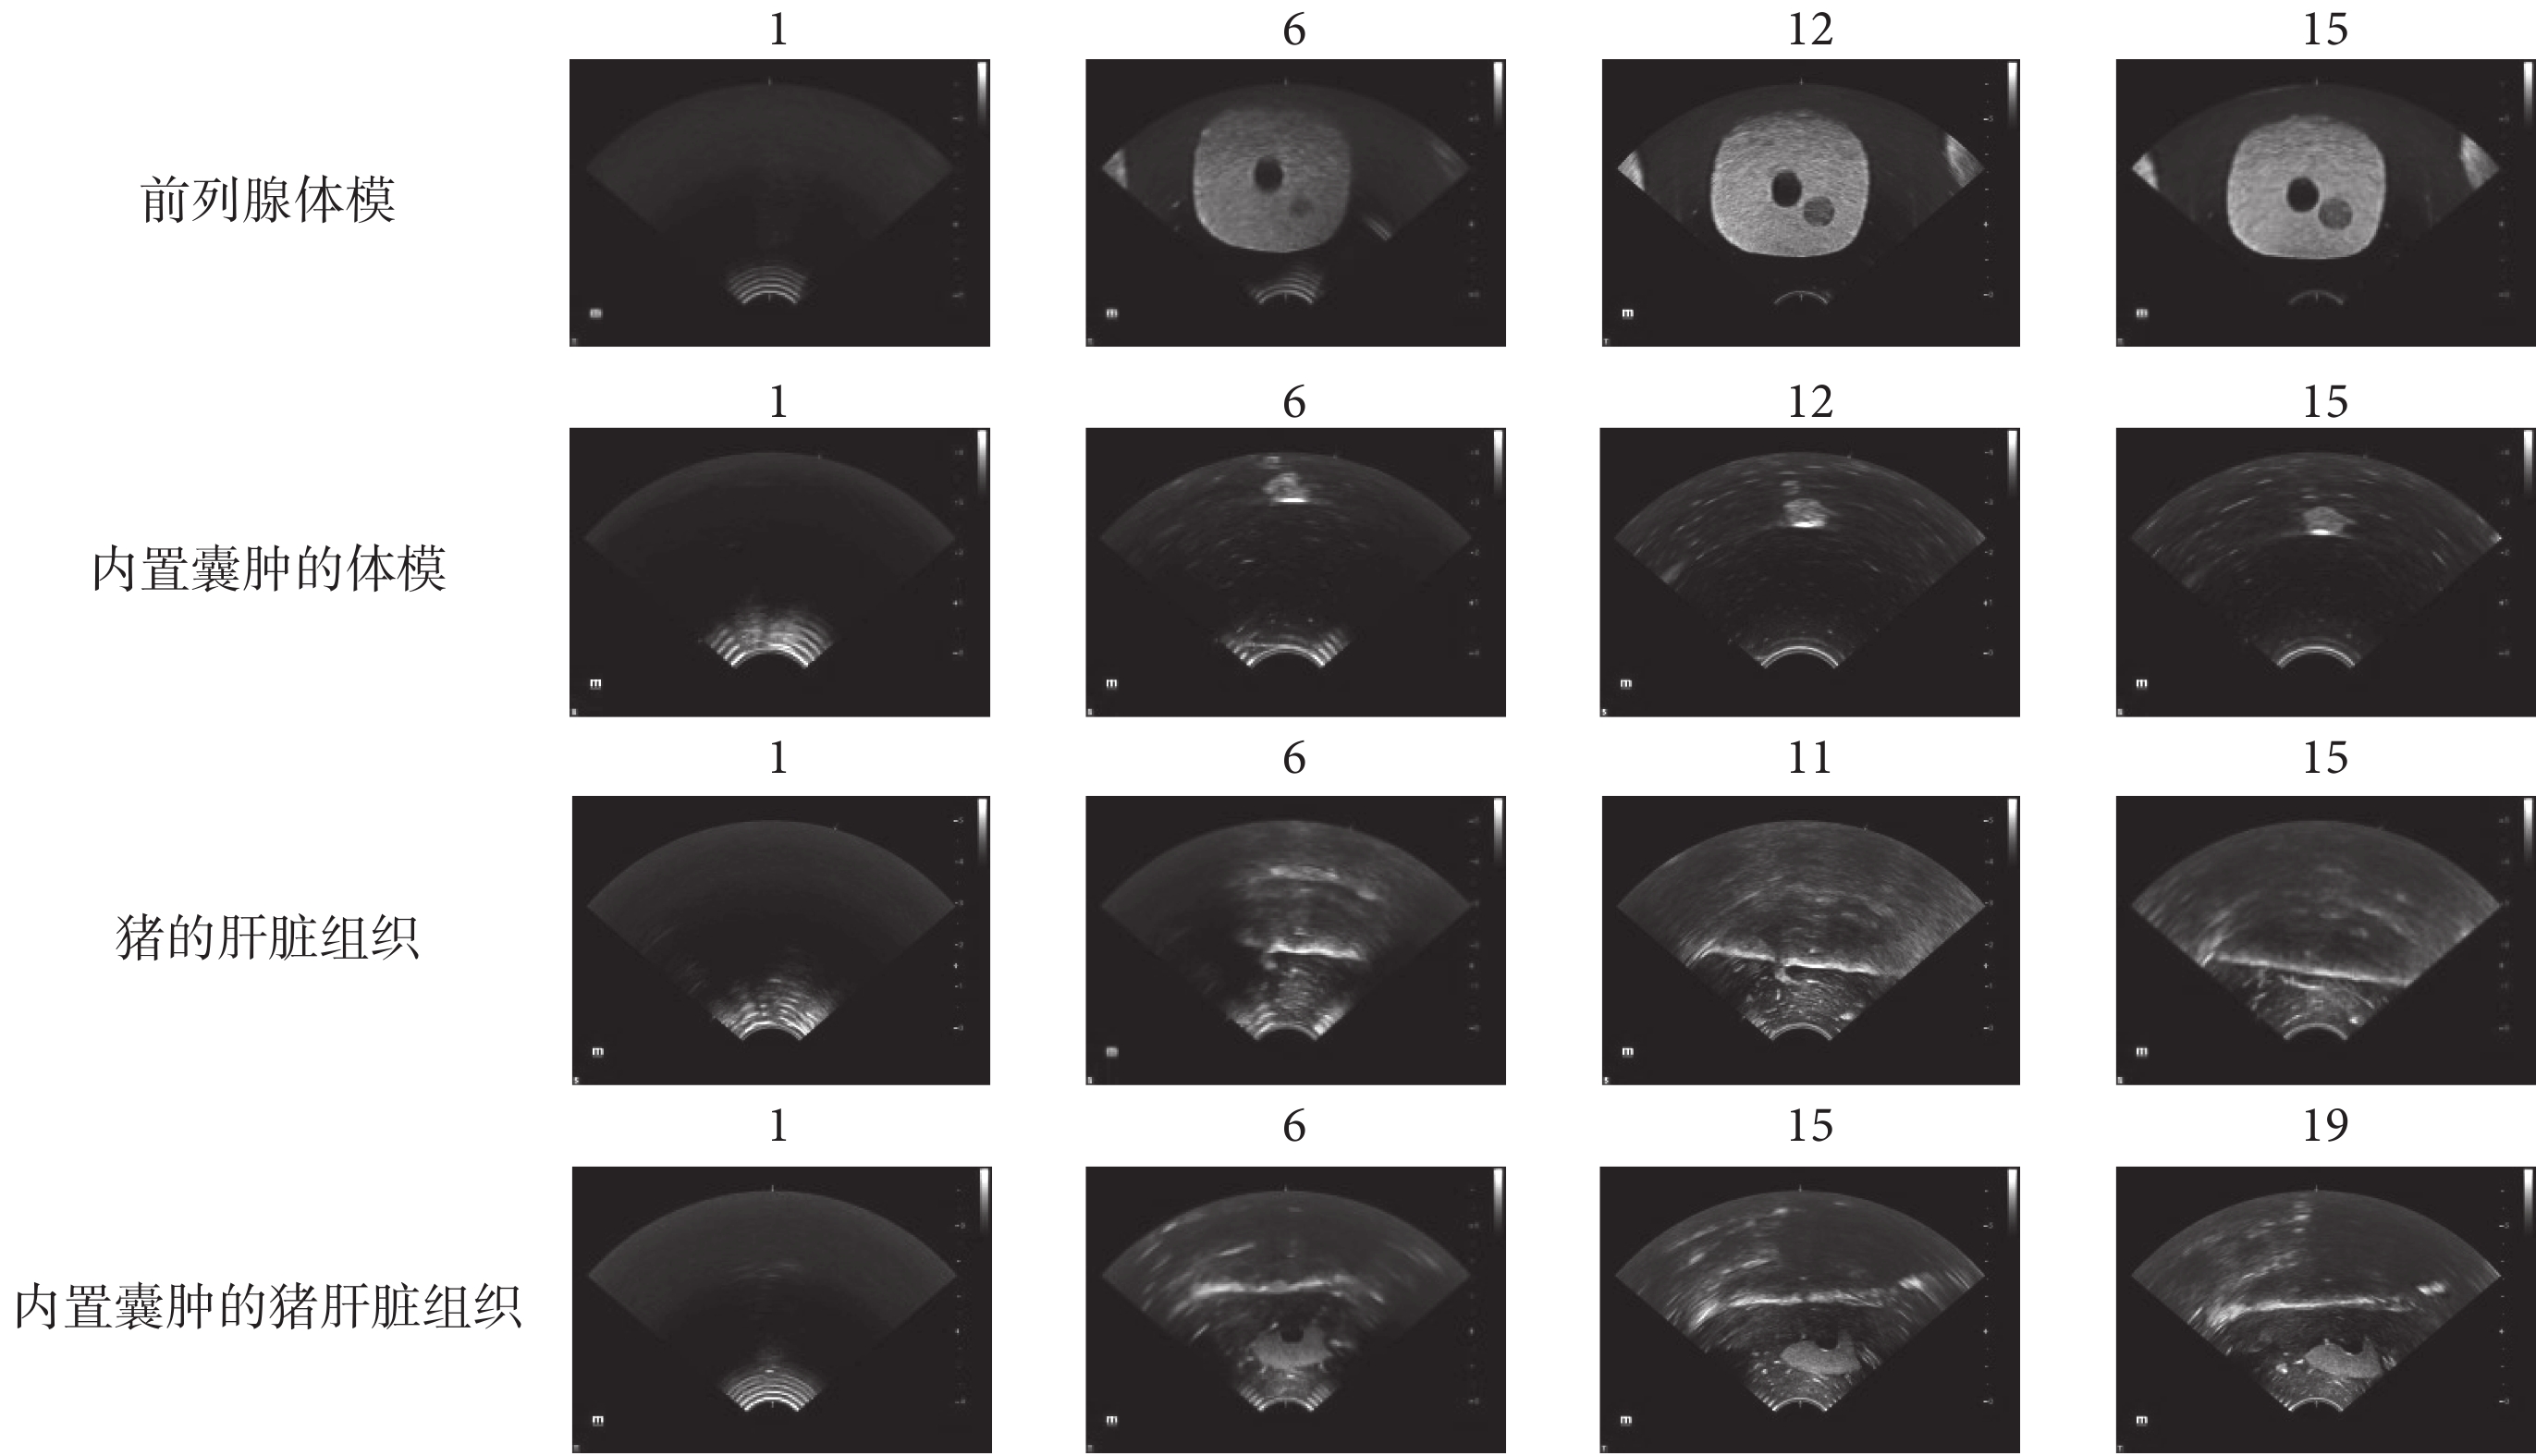

實驗過程中,一共采集4組二維超聲圖像,共計81張。圖像大小為1 050 × 720,橫向和縱向分辨率為0.18 mm/像素。機器人采集的部分超聲圖像如圖3所示。其中,前列腺體模的圖像15張,豬的肝臟組織的圖像21張,內置囊腫的豬肝臟組織圖像25張,內置囊腫的體模圖像20張。圖3中的超聲圖像在測試圖像組的編號分別標于圖片上方,其中編號為1的超聲圖像均為每組的首幀圖像。